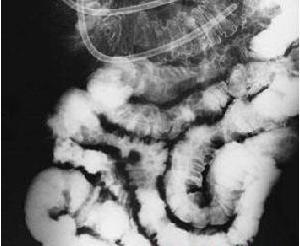

嵌杯樣病毒胃腸炎血清學檢測圖解流行病學 在秋冬季發生的水樣腹瀉,尤其有較多病例同時發生,應考慮有本病可能;

依賴病原學及血清學檢測確診。可用電鏡或免疫電鏡從患者糞便中查見病毒顆粒,或用 ELISA 或 RIA 法檢查患者糞便中病毒特異性抗原和患者血中特異性抗體。可用電鏡或免疫電鏡從患者糞便中查見病毒顆粒,或用 ELISA 或RIA 法檢查患者糞便中病毒特異性抗原和患者血中特異性抗體。